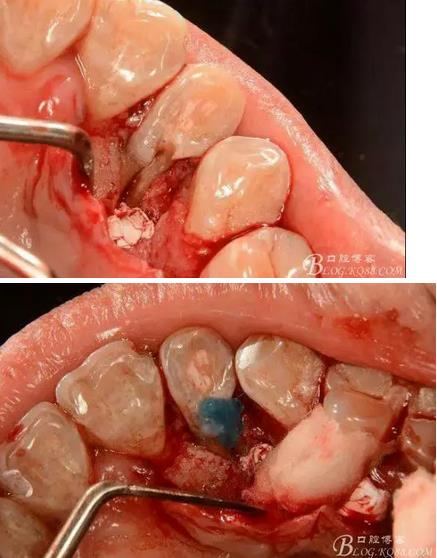

(1) 檢查:12唇側(cè)牙齦可見竇道,牙體顏色較鄰牙暗,無光澤,形態(tài)完整無缺損,唇側(cè)及近遠中向未提及牙周袋。腭側(cè)齦緣輕度紅腫,舌側(cè)窩可探及裂溝,可見浸墨狀痕跡,沿裂溝舌側(cè)探診牙周袋深大于11mm,除患牙外全口牙周狀況良好,為探及牙周袋,牙齦色粉紅。邊緣菲薄,質(zhì)地堅韌。12冷熱診無反應(yīng),叩診(+-),無明顯松動,無咬合創(chuàng)傷。12根尖x線片示,根管中三分之一中可見一斜向線樣透射影像根尖區(qū)及遠中根三分之一可見低密度透射暗影,錐形束CT示12根尖區(qū)唇腭向骨吸收已穿通,根面溝達根中三分之一卷曲分出另一牙根,再未見其他明顯的根管系統(tǒng)。

(3) 處理:常規(guī)開髓,修整髓腔,15#k銼探查根管,根管測量儀確定工作長度,根長22mm,大錐度手動銼完成根管預(yù)備,沒換一次銼沖洗根管一次,消毒,干燥根管,暫封維他派克斯。4%阿替卡因腎上腺素行11至14局部浸潤麻醉、消毒、鋪巾,做11-14腭側(cè)牙齦水平切口并翻瓣暴露12腭側(cè)骨缺損區(qū),清理肉芽組織及壞死骨組織,清潔術(shù)區(qū),磨除根面溝,制備固位溝槽,酸蝕,粘接,光固化樹脂修復(fù)根面缺損區(qū),阻斷牙周感染途徑。拋光樹脂,沖洗創(chuàng)面,復(fù)位齦瓣,局部敷料壓迫一分鐘,對位縫合齦瓣。術(shù)后抗炎治療,7d線。